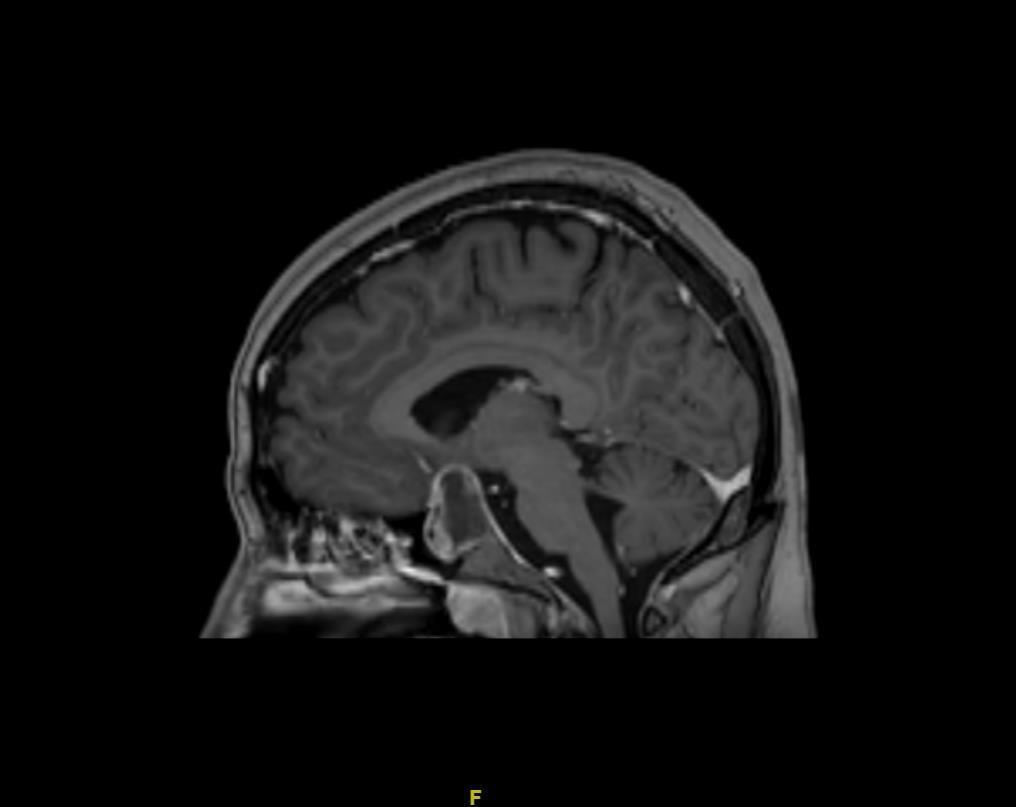

Le patient bénéficie également d’une imagerie par résonance magnétique (IRM) cérébrale devant un doute sur le scanner. Voici deux coupes (figures 2 et 3) :

Figure 2 (source : G. Kielwasser)

Question 10 - Les réponses justes à propos de ces coupes sont les suivantes :

Sur la coupe coronale d’IRM en séquence T1 avec injection de gadolinium ci-dessous (figure 2 bis), on constate :

– sur l’image de gauche, que les sinus caverneux sont visibles de part et d’autre de la fosse pituitaire avec les vaisseaux rehaussés par le gadolinium. La flèche jaune pointe la masse hétérogène (centre hyposignal, périphérie hypersignal), en lien avec l’apoplexie pituitaire qui correspond à une hémorragie au sein du macro-adénome hypophysaire ;

– sur l’image de droite, que la ligne rouge correspond à une limite approximative de la loge pituitaire que l’hypophyse ne devrait pas dépasser. La flèche verte pointe le chiasma optique comprimé par la masse.